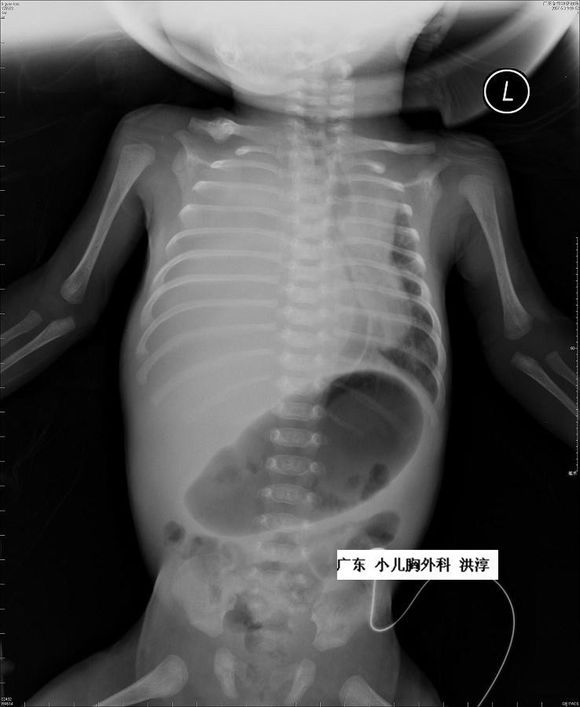

对于胎龄大于32周的胎儿胸腔积液,出生后在建立静脉通路,保证体循环血容量的情况下给予胸腔穿刺并密切观察可能是最好的选择。

对小于32周的FHT胎儿,有3种方式提供选择:胸腔穿刺术、胸腔羊膜腔分流,以及胸腔-母体皮下引流。但应该关注的是,这些操作均有可能出现感染、出血、胎膜早破、早产及损伤胎儿的风险。

胸腔-羊膜腔分流术的胎儿在娩出后需夹闭或拔除引流管避免新生儿气胸的发生。如接受宫内治疗的胎儿胸腔积液仍进行性增多,可考虑在妊娠35 ~ 36 周时终止妊娠,并且在产后进行新生儿胸腔穿刺术提高新生儿的存活率。